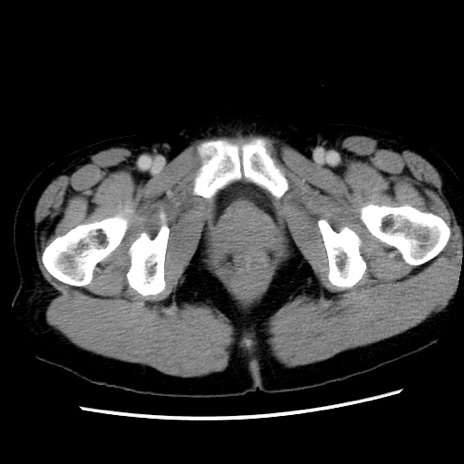

症例10(横断像)

【症例】 50歳代女性

【主訴】 腹痛

【現病歴】前日生レバーを食べた。今朝に排便あり。 昼前に突然発症の腹痛を生じ、当院救急外来を受診した。

【既往歴】 子宮筋腫にてで子宮全摘後

【身体所見】 意識清明、腹部:平坦、軟、下腹部やや左を中心に圧痛・反跳痛あり、筋性防御あり

【データ】WBC 7800、CRP 0.07